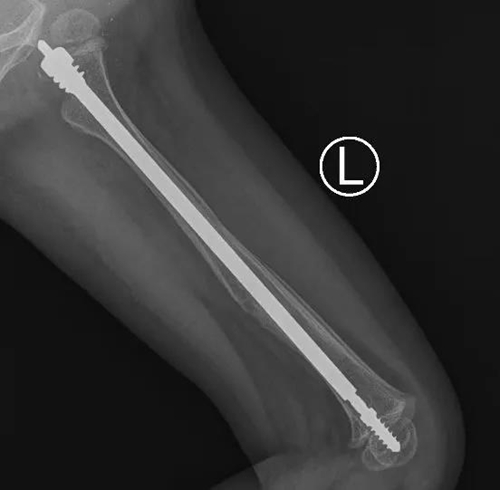

近日,青島婦女兒童醫(yī)院小兒骨科成功為一名患有“脆骨病”(又名成骨不全癥)的2歲患兒進行了“左側(cè)股骨骨折可延長髓內(nèi)針內(nèi)固定術”治療,這是可延長式髓內(nèi)針在省內(nèi)首次應用于“脆骨癥”患兒的骨折治療。

小兒骨科團隊多次討論后,決定采用一種專門針對成骨不全的全新手術方式:兒童可延長式髓內(nèi)針內(nèi)固定術。這種髓內(nèi)針可以應用于大腿、小腿、上臂等長骨骨折。隨著孩子的生長,可延長髓內(nèi)針自動滑動延長,加強了患兒骨質(zhì)的強度,減少再次骨折的幾率。

在完善各項檢查和準備后,小兒骨科團隊在麻醉科、手術室的配合下為彤彤進行了微創(chuàng)手術。術中,主刀醫(yī)生小兒骨科主任董震將直徑為3.0mm的針芯和4.8mm的可延長彈性髓內(nèi)釘系統(tǒng),精準的置入股骨髓腔內(nèi)完成復位和固定。手術耗時僅1.5個小時,骨折部位并無手術切口,僅在遠離骨折的肢體近端有個微創(chuàng)手術切口,術中出血僅5ml。目前彤彤恢復良好,已經(jīng)康復出院。